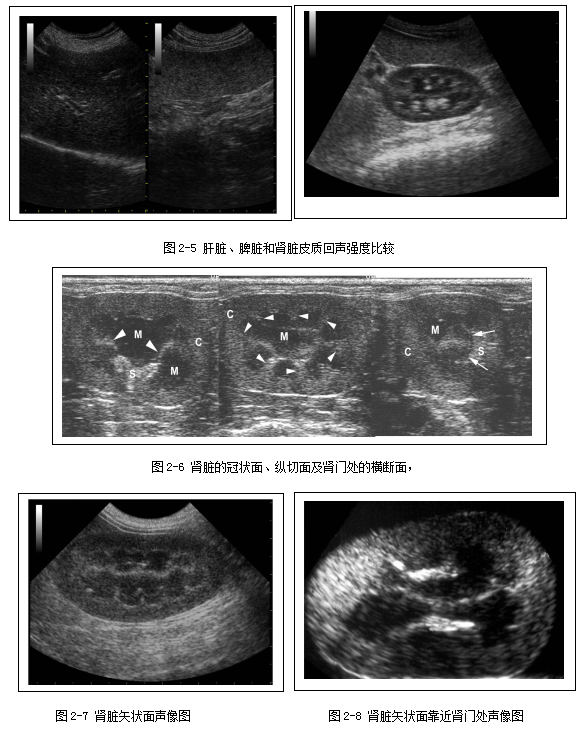

左右两侧肾脏大小相当;肾脏的包膜呈现为高回声;肾脏皮质回声强度略低于或等于肝脏回声,显著低于脾脏回声(2-5);肾脏髓质与皮质相比,髓质呈低回声结构(2-6)。猫的肾脏中由于皮质内脂肪细胞聚集,所以有时猫的肾脏皮质回声强度会高于肝脏回声。在肾脏矢状面上可显示中等回声的肾脊,其为肾髓质的延伸部分,与肾盂接触;此外肾脏矢状面上还可显示肾柱,为皮质向髓质内的延伸,将髓质分成一个个肾椎体(图2-7)。再略微靠近肾门处的肾脏矢状面,还可显示肾窦呈平行的两条高回声带状结构(图2-8)。弓形血管的管壁呈成对的、短线高回声结构,位于皮质髓质交接处。正常犬猫的肾盂偶尔可见,高分辨率的探头有助于肾盂的显影。正常犬猫的肾盂憩室和输尿管除非扩张,否则在超声上是不可见的。